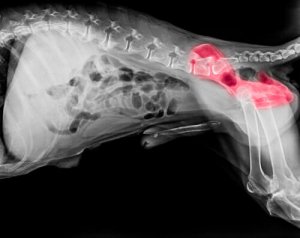

A melhor maneira de confirmar o diagnóstico é levar o seu animal de estimação a um veterinário para que ele faça os exames físicos adequados. Um raio-X geralmente é o exame definitivo para confirmar a displasia de quadril em cães.